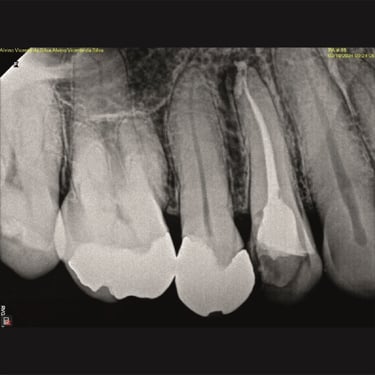

CASOS CLÍNICOS ENDO

Abaixo você encontra fotos de alguns dos tratamentos realizados.